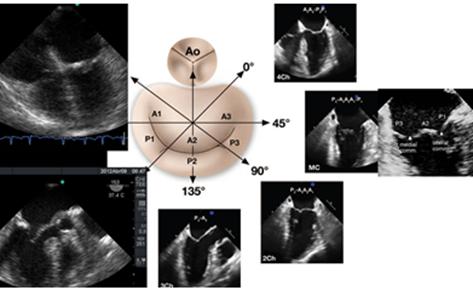

El análisis anatómico ecocardiográfico, se realiza con 2 D, y se basa en la adquisición de distintos planos que nos permitan observar el anillo, los velos y las comisuras en varias proyecciones.(Figura 7) Siguiendo un protocolo de 8 planos, que incluye 3 planos a nivel medio esofágico a 0° superior, donde se visualiza A1 y P1 además de la aorta y la orejuela, medio donde se ve A2 y P2, e inferior, casi llegando al seno coronario donde se encuentra A3 y P3. Luego entre 60° y 90°, a nivel del plano comisural, se ve P1, A2 y P3. Entre 80° y 100° en el plano de 2 cámaras, obtenemos la visión de A1, A2 y P3; con pequeños giros desde este lugar, podemos analizar todo el velo posterior y A2 y A3. Por último en esófago medio, el plano de 120° permite evaluar A2 y P2.(11)

Figura 7 Esquema de VM e imágenes de 4, 3 y 2 cámaras para comprender los distintos segmentos observados de las valvas mitrales, según el ángulo de visualización.

La imagen que nos permite ver integralmente ambas valvas y sus respectivos segmentos es la vista transgástrica a 0° (Figura 8) y la que nos facilita el estudio anatómico del aparato subvalvular y los músculos papilares es la transgástrica entre 80°-130°